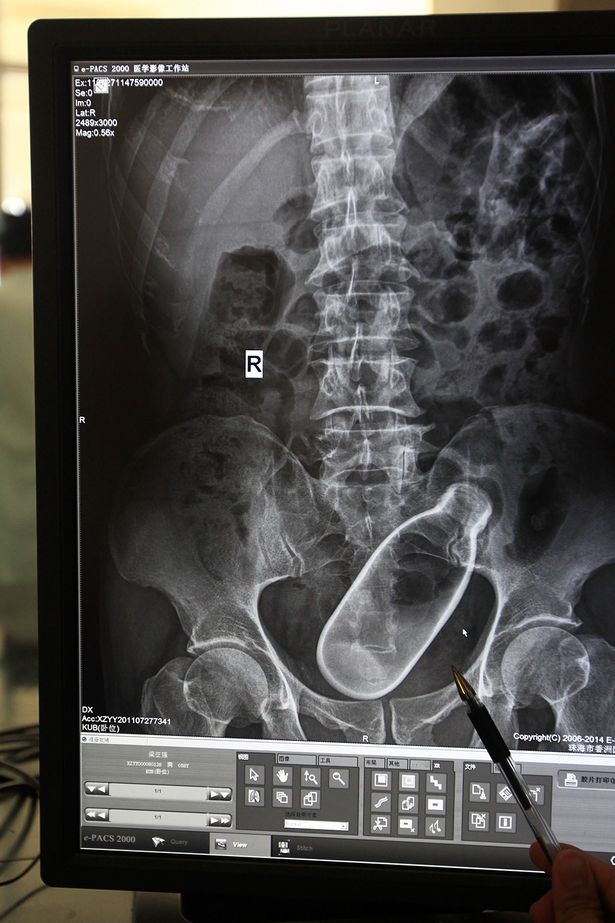

ZHUHAI (CINA) – Un 60enne di Zhuhai, città della provincia cinese di Guangdong, viene ricoverato in ospedale per una forte stitichezza. I medici lo sottopongono ai raggi X e scoprono che nell’intestino dell’uomo si trova una bottiglia di vetro entrata lì solo in un modo: attraverso l’ano.

L’uomo sostiene di soffrire di una forte stitichezza e spiega di aver utilizzato la bottiglia per provare a stimolare l’intestino. Dopo aver inserito la bottiglia, non è però riuscito più a rimuoverla.

La foto è diventata virale ed è stata diffusa in Rete dai medici dell’ospedale. Fortunatamente per lui, il nome dell’uomo di 60 anni non è stato reso noto.